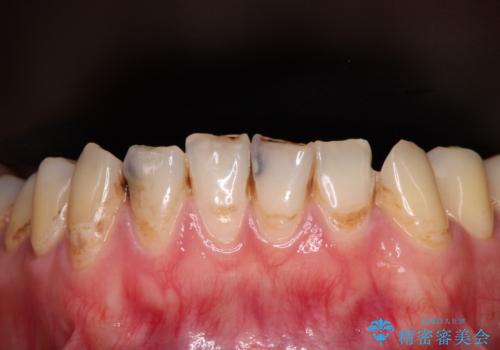

むし歯だらけの前歯をオールセラミッククラウンできれいに

- 上下前歯や奥歯の虫歯治療を希望して来院された患者様です。

全顎的にむし歯が多く、根管治療の必要奥歯や、審美的に気になっている前歯を中心にオールセラミッククラウンにて補綴治療を行うこととしました。

上顎前歯は歯肉退縮により歯根が露出していたため、事前に歯肉移植術により根面被覆を行い、その後にオールセラミッククラウンを装着することとしました。